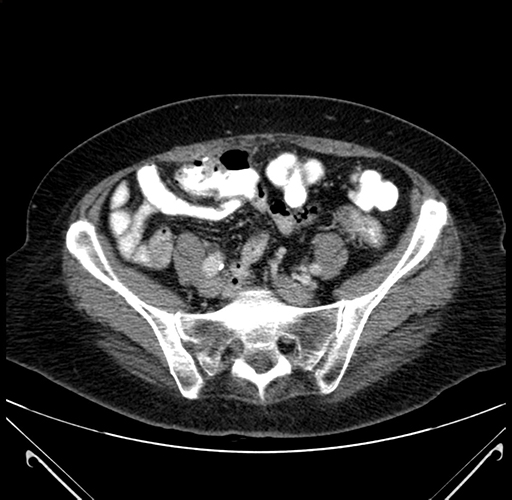

Axial Venous

Coronal Venous